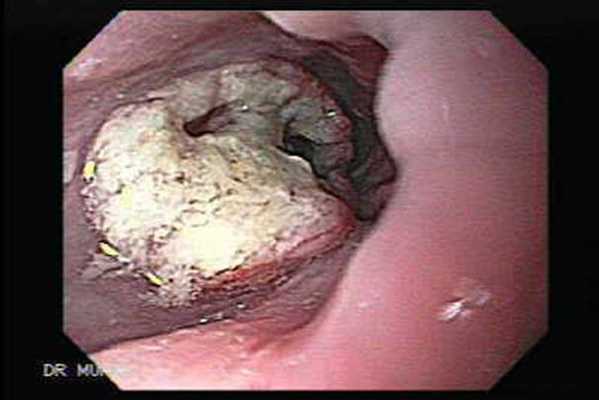

(Слева) При эндоскопической ультрасонографии выявлено внутрипросветное объемное образование, не проникающее через мышечную пластинку (аденокарцинома на стадии Т1а). Внутрипросветная сонография - лучший метод для определения глубины инвазии опухоли.

(Справа) На фотографии, полученной при эндоскопическом исследовании у этого же пациента, видно неправильной формы полиповидное объемное образование в дистальных отделах пищевода. Эта аденоарцинома была оперативно удалена путем эзофагэктомии с перемещением желудка в грудную полость.